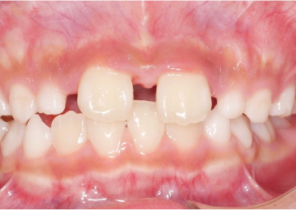

Case Report 1

10 years 0 months old, 18 stages of Invisalign Palatal Expanders

Courtesy of Dr. Sandra Khong Tai

Pre Invisalign Palatal Expander Expansion

Post Invisalign Palatal Expander Expansion

After Invisalign First treatment